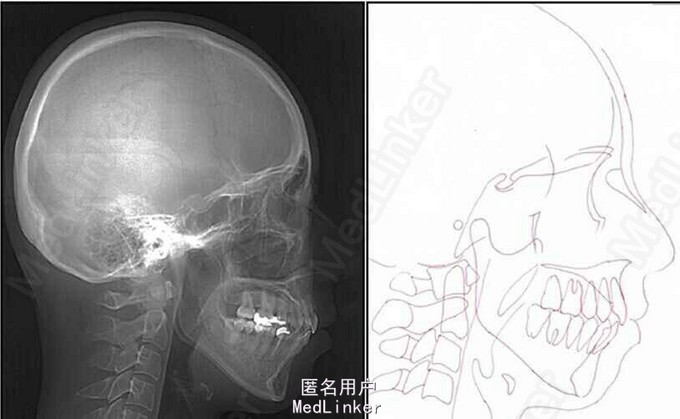

面部:凸面型,上下唇前突,上唇E线前3.5mm,下唇E线前9.5mm,闭唇时口周肌肉紧张。口内检查:双侧尖牙磨牙I类关系,左侧7锁合,覆盖4.5mm,覆合1mm,中线正,上颌拥挤度12.5mm,下颌拥挤度8.2mm。全景片示4个第三磨牙均阻生,怀疑上颌第二磨牙远中面因8阻生有牙根吸收,下颌8近中倾斜阻生更严重,右下6、左下4和5都行了RCT并大面积充填。头影测量示骨性I类,高角,下切牙唇倾。无TMJ症状,只是咀嚼测试时,右侧(非锁合侧)较左侧速度更快且更稳定。

诊断:安氏II类1分类,双颌前突,牙列严重拥挤,左下7锁合,双侧上7牙根吸收,四颗第三磨牙阻生 治疗目标:减少唇的突度及前牙拥挤,扶正4颗阻生的第三磨牙,达到良好的面部美观和功能咬合。 治疗:上颌拔除2颗5和2颗7(不拔4的原因为左上4为正常牙,左上5大面积充填;右上4形态较右上5好。因拔除了坏牙保留了健康牙齿,但是拔5不利于前牙的内收,所以于上后牙56之间植入了支抗钉加强支抗,辅助内收前牙。拔7原因为两颗7远中面均有牙根吸收且有大面积充填),下颌左侧拔除5和7(左下5根管治疗且根尖阴影,拔除左下7原因为严重锁合,改正困难且容易导致上下磨牙的伸长加重II类高角面型),右侧拔除根管治疗且大面积充填后的6;分别竖直4颗近中倾斜阻生的8,整个疗程39个月,四颗8成功的代替6或7。双侧I类尖牙关系,左侧磨牙I类关系,右侧磨牙完全远中关系。唇突度改善,全景片可见达到可接受的牙根平行度,4个8完全萌出直立。以前因为锁合导致的两侧咬合不对称没有了。